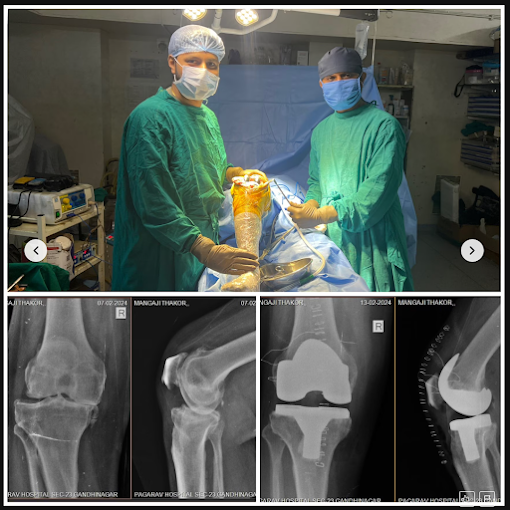

Dr. Dhruv D. Patel

MS Ortho, FIJRS, FIAAS

Joint Replacement and Trauma Surgeon

7 + years of experience

10k+ successful surgeries.

My mother had a successful knee replacement at Ved Orthopedic Hospital. Dr. Dhruv Patel's expertise, compassionate care, and advanced treatment made her recovery smooth. She’s now walking pain-free and confident again. Truly grateful!

My father underwent total knee replacement surgery under the care of Dr. Dhruv Patel, and we couldn't be more satisfied. Dr. Patel is highly knowledgeable, skilled, and exceptionally kind in his approach. His guidance and care throughout the treatment made the entire journey smooth and reassuring. We are truly grateful for his expertise and recommend him to anyone seeking orthopedic care in Gandhinagar.